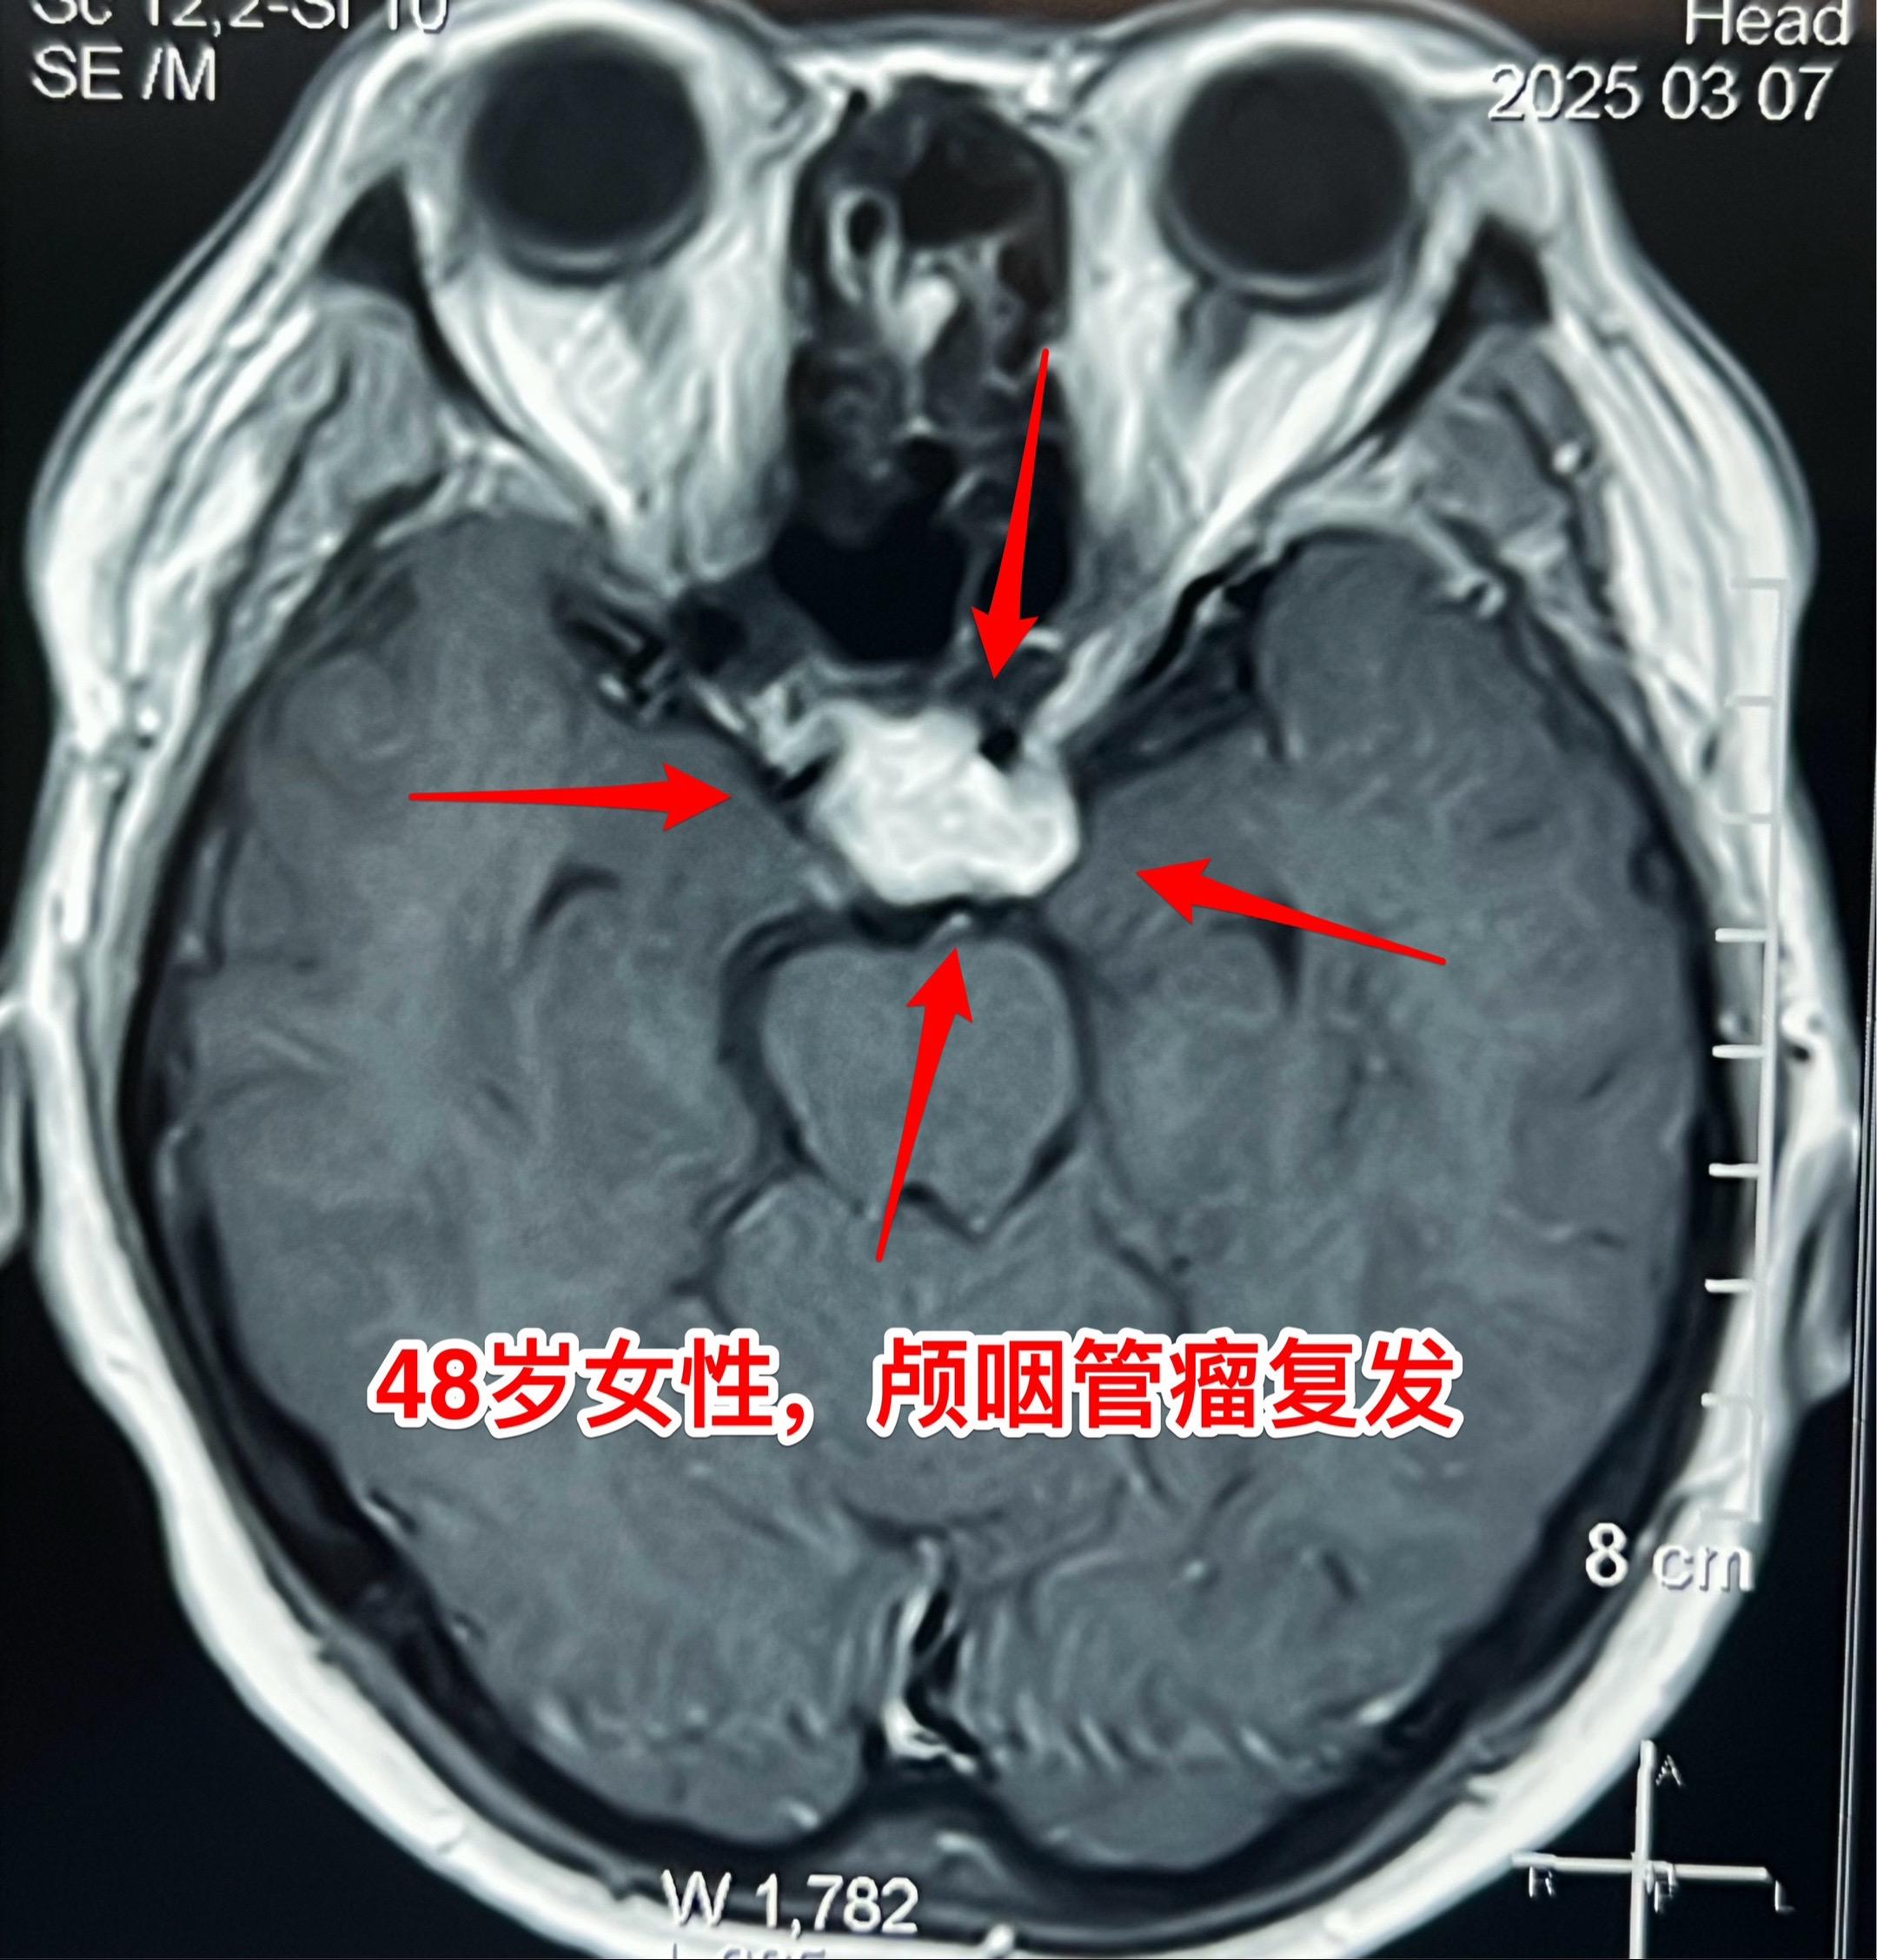

今天的第二个颅咽管瘤手术。48岁女性,洛阳市人。因颅咽管瘤先后行经鼻手术和开颅手术各一次。开颅手术是在24年12月作的,手术后又出现右眼视力下降,复查磁共振显示肿瘤复发,见图。 这个肿瘤看起来似乎难度不大,其实不然。距离前一次手术刚刚三个月,瘢痕粘连紧密而且肿瘤向左右两侧均嵌入视神经-颈内动脉缝隙内。这是乳头型颅咽管瘤,很有难度!